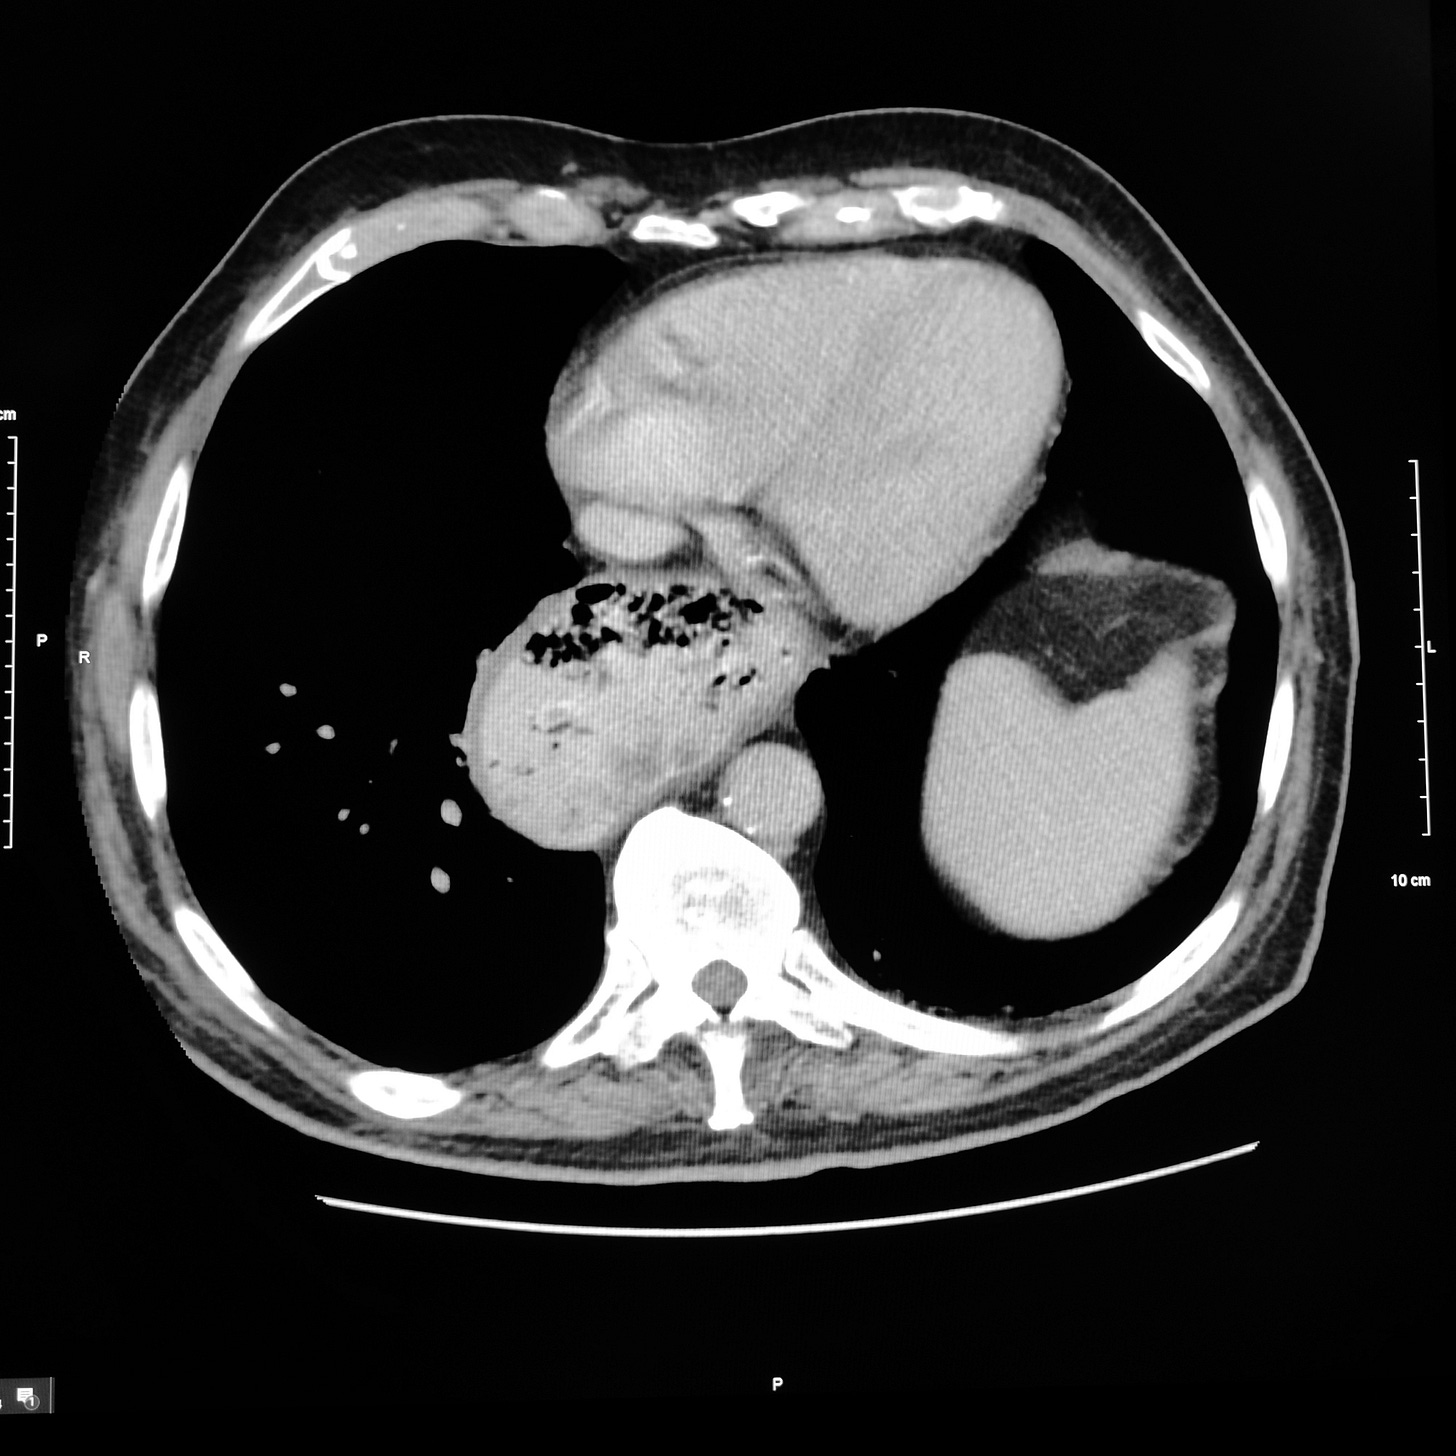

QuizNausea and vomiting for several monthsChestAlexander BaxterFeb 01, 2024ShareWhat is the diagnosis? What can cause this problem?Leave a commentClick here for diagnosis and discussionPreviousNext